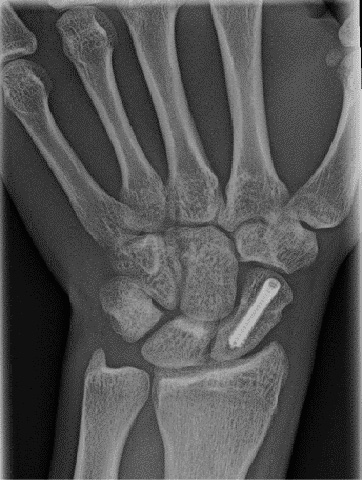

Skafoid Kemik Kırığı ve Tedavisi

Skafoid Kemiği Kırığına Dikkat!

Eğer kırık yerinden oynamamışsa genellikle alçıyla tedavi edilir. Bu kemiğin iyileşmesi normal kemiklerden daha uzun sürer. O yüzden alçı en az 9 hafta kalır. Eğer kırık kaymışsa o zaman cerrahi yönteme başvurmak gerekir. Ameliyatta kırık kapalı veya açık yöntemle kırık anatomik olarak düzeltilir ve kaynayana kadar bu pozisyonda kalması için bir takım vidalar ile sabitlenir. Skafoid kırığı tedavisinin zahmetli ve aylar süren bir tedavi olduğu unutulmamalıdır. Bazen kaynamanın sağlanamaması nedeni ile ikinci bir cerrahi girişimin gerekliliği ortaya çıkabilir. Kaynama sonrası ise kemiğin damarsal beslenmesi MRI ile iki yıl süreyle izlenir.